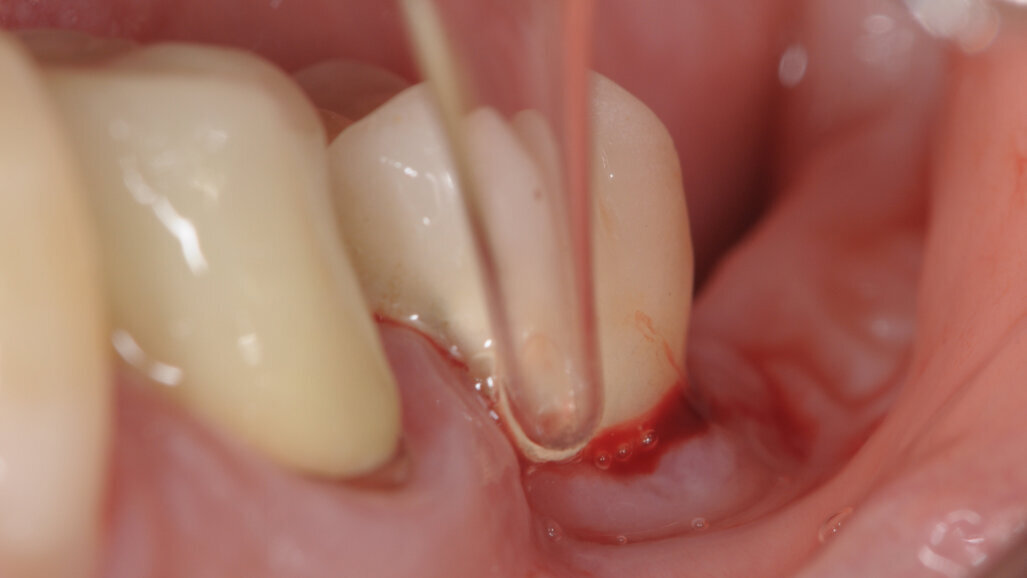

La paziente è stata trattata con protocollo Full mouth disinfection e nello specifico dell’impianto affetto da perimplantite in zona 36, è stata effettuata nella seduta operativa una strumentazione ultrasonica con inserto in PEEK per la rimozione del biofilm e delle concrezioni minerali. In seguito il sito è stato sottoposto a perio polishing con glicina e irrigazione della tasca perimplantare con H2O2. Successivamente è stata eseguita la prima applicazione di ozono.

Il paziente viene visto per 2 volte a settimana e la seduta viene eseguita con una rimozione meccanica del biofilm tramite utilizzo di polveri di glicina, lavaggio con H2O2 e successiva applicazione di ozono con tecnica prima descritta.

La paziente viene sottoposta alla medesima seduta fatta nei primi 15 giorni con variazione nella frequenza portata ad 1 applicazione per settimana (Figg. 1-6).

A termine del trattamento descritto in precedenza da un punto di vista clinico abbiamo ottenuto un ripristino dei parametri di salute dell’impianto ovvero la scomparsa del sanguinamento dell’edema e della purulenza, in oltre si è verificata una riepitelizzazione dei tessuti molli limitrofi l’impianto. Da un punto di vista radiografico abbiamo ottenuto la neoformazione di osso attorno alle spire dell’impianto (con relativo aumento della stabilità) che a inizio terapia era da considerarsi potenzialmente come perso. La radiografia a 60 gg prima ed a 1 anno mostrano quanto prima descritto, ovvero un ripopolamento di componenti cellulari ossei sull’impianto con un recupero di 3 spire implantari (Figg. 7-9).